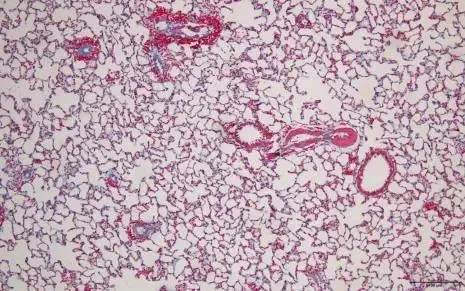

图片

改良Masson三色染色液-正常小鼠肺组织